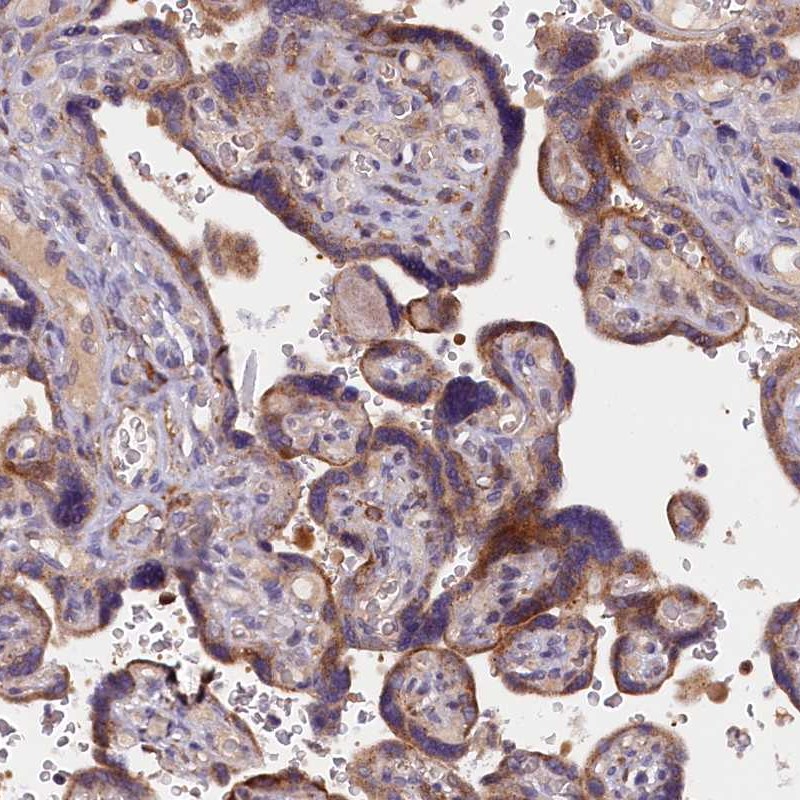

Immunohistochemical staining of human placenta shows moderate cytoplasmic positivity in trophoblastic cells.